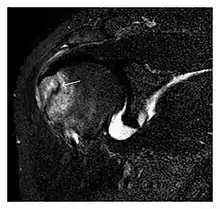

The greater tuberosity of the humerus is also an illustrative location of occult fractures. The osseous injury may follow seizures, glenohumeral dislocation, forced abduction, or direct impaction. They are commonly discovered on MRI in symptomatic patients with suspicion of rotator cuff tear. Coronal images are best suited for detection. They appear as crescentic oblique lines surrounded by a bone marrow edema pattern (Figure 5). The rotator cuff must be inspected since associated ligamentous lesions are common. In the ankle, malleoli and tarsal bones should be checked carefully for any cortical disruptions and radiolucent lines that may reveal a fracture. Awareness of the exact location of the pain will help direct the attention of the interpreter when searching for very subtle signs of fracture (Figure 6).[1]

Fatigue fractures are more frequent in women which may be due to the relatively smaller bones of women. Moreover, pregnancy is a well-recognized risk factor for femoral neck fatigue fracture. While fibular and metatarsal fractures have a low risk of complications, other sites including the femoral neck, midanterior tibia, navicular, talar, and other intraarticular fractures are prone to complications such as delayed union, nonunion, and displacement. The site of the insufficiency fracture may be specific to the activity: for example, rugby and basketball players are more prone to navicular fractures, while gymnasts have a higher risk for talar fractures (Figure 7). Long distance runners are at increased risk for pelvic, tibial (Figures 8 and 9), and fibular fractures. In the military, calcaneus (Figure 10) and metatarsals are the most commonly cited injuries, especially in new recruits. Billiard players are at risk for upper limb fractures (Figure 11).[1]

a

b

Figure 7: Fatigue fracture of the talus in a 25-year-old male basketball player with right hind foot and ankle pain, without history of trauma, and a normal initial radiograph (not shown). (a) One-month followup lateral radiograph shows normal appearance. (b) Sagittal T1-weighted MRI shows an irregular fracture line (arrow) within an ill-defined area of hypointensity corresponding to bone marrow edema.[1]